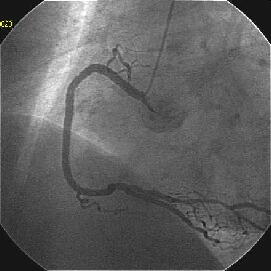

Crush���KBT.

|

|

|